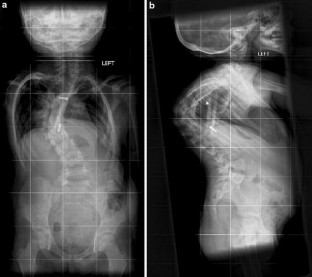

In this Grand Round, we present the case of a 7-year-old girl with a severe scoliosis and thoracic insufficiency syndrome (TIS). 3D CT reconstruction imaging demonstrated a mixed picture of fusion and segmentation abnormalities. A marked kyphoscoliosis was demonstrated at the thoraco-lumbar junction. Via a left thoracotomy, anterior excision of intervertebral discs was performed together with, interbody fusion, and in situ stabilisation of the kyphosis with double allograft (femur) strut grafts.